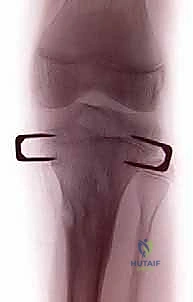

3. الجراحة الحديثة: نمو العظام الموجه (Guided Growth)

هنا يتجلى الإبداع الطبي. بدلاً من كسر العظم، نستخدم صفيحة صغيرة جداً (غالباً على شكل رقم 8 - Eight-Plate) يتم تثبيتها بمسمارين صغيرين على أحد جانبي صفيحة النمو. هذه العملية تستغرق وقتاً قصيراً جداً، وتتم من خلال جرح لا يتعدى 2-3 سم.

- تثبيت الصفيحة (Eight-Plate): يتم وضع شريحة معدنية صغيرة جداً (تشبه رقم 8) بحيث يكون منتصفها فوق صفيحة النمو مباشرة.

- إدخال المسامير: يتم إدخال مسمار في النصف العلوي من الشريحة (في المشاشة - Epiphysis) ومسمار آخر في النصف السفلي (في الكردوس - Metaphysis). هذه المسامير تعمل كمفصلة (Hinge) تسمح بنمو العظم في الجانب الآخر بينما تقيد النمو في هذا الجانب.